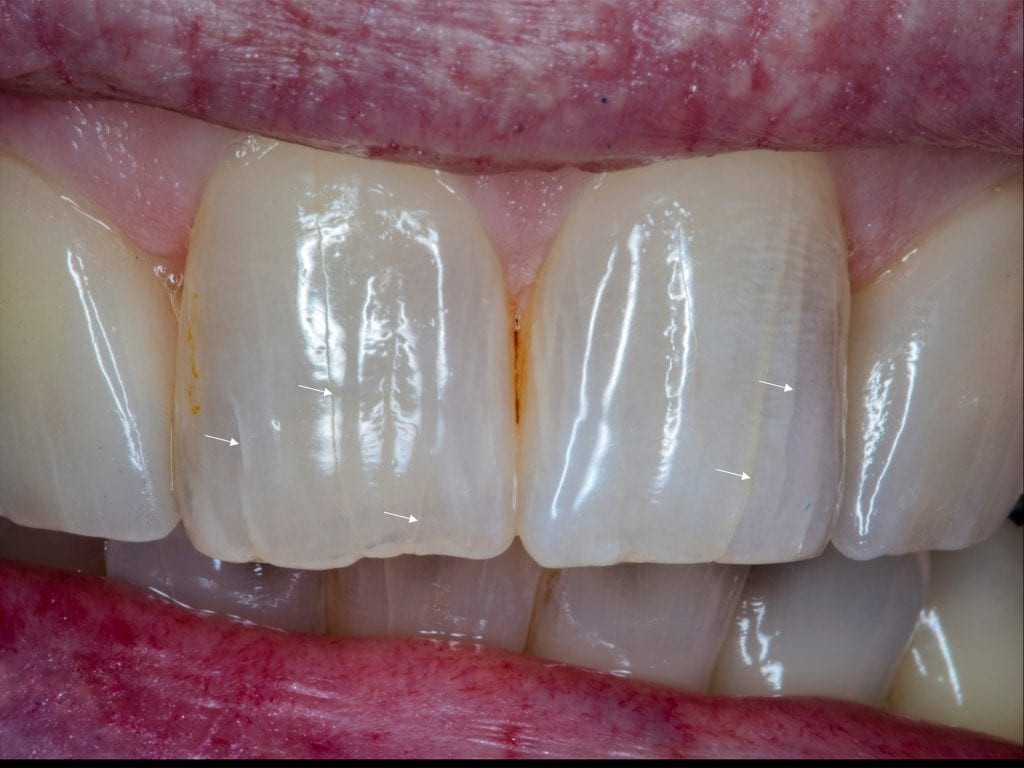

Các tổn thương rạn men răng xuất hiện đặc trưng ở nhóm răng cửa và nhóm răng hàm nhỏ với các đường rạn chạy dọc theo mặt ngoài các răng. Theo thời gian, các đường rạn có thể bị nhiễm màu ngoại sinh với các lõm dọc phổ màu từ vàng tới nâu đen. Dưới các lát cắt kính hiển vi quang học, người ta thấy rằng các tổn thương rạn men chỉ nằm khu trú ở bề mặt men răng, không vượt quá đường ranh giới men ngà. Các đường rạn men răng thường không gây ê buốt, đau đớn và không ảnh hưởng nhiều tới chức năng ăn nhai, tuy nhiên, sự xuất hiện các rãnh lõm dọc thân răng này ảnh hưởng tới vấn đề thẩm mỹ.

Rạn men răng là các đường lõm dọc khu trú trên mặt ngoài ở men răng

Rạn men răng, với sự truyền sáng đồng nhất trên bề mặt răng |